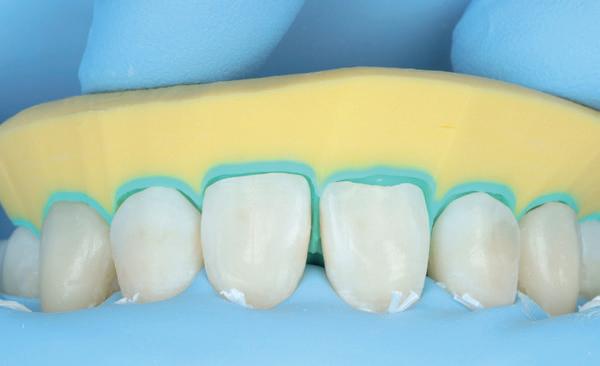

Vervaardigen essix retainer met dummies waarbij er een emergence profile van de 11 en 21 werd gevormd door eivormige dummies 4 mm in de gingiva te plaatsen

• Aanvulling zachte weefsels met de VISTA techniek en een vrij gingivatransplantaat uit het palatum links en direct dragen van de essix retainer

Na 4 weken intra-orale scan voor de etsbrug en kleurbepaling bij de technicus

• Plaatsen van de etsbrug met een composietcement

Voordat er gescand kon worden voor een etsbrug, werd een studiemodel vervaardigd om met de technicus te overleggen of er voldoende ruimte was voor 2 centrale incisieven in de mesio-distale zin en of er voldoende ruimte was in occlusie voor de vleugels van de etsbrug. Er hoeft enkel nog aan de 12 en 22 pala-